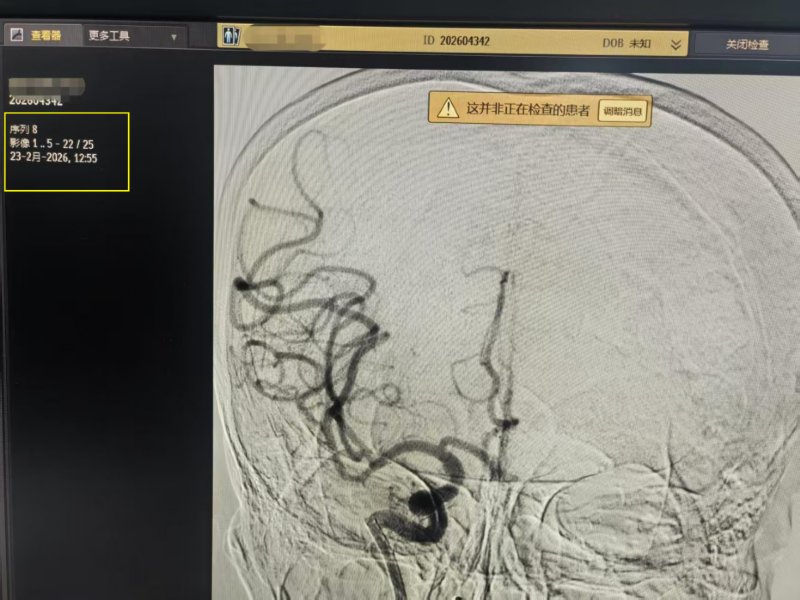

12:34完成病变处造影提示右侧大脑中动脉闭塞

12:55完成手术造影提示右侧大脑中动脉顺利开通